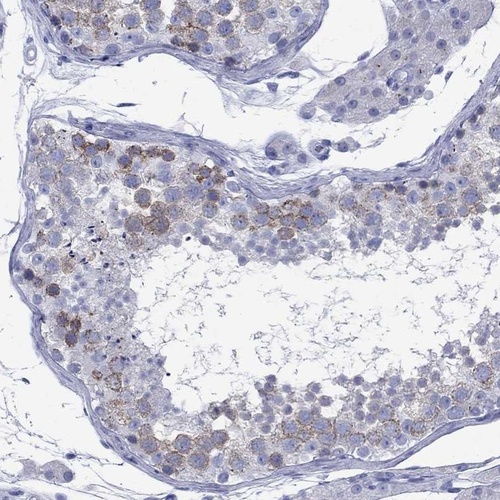

Immunohistochemistry analysis in human testis and liver tissues using Anti-CCNA1 antibody. Corresponding CCNA1 RNA-seq data are presented for the same tissues.